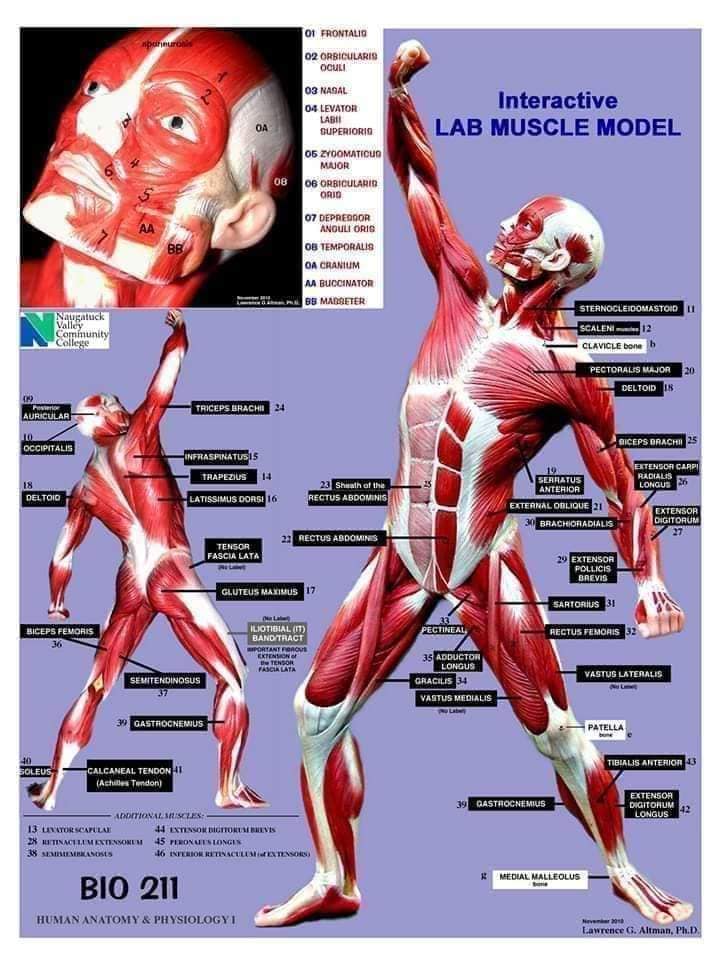

Скелетно-м'язова система людини (синоніми: Опорно-рухова система, опорно-руховий апарат, кістково-м'язова система, локомоторна система) — комплекс структур який утворює каркас, надає форму організму, дає йому опору та забезпечує захист внутрішніх органів і можливість пересування у просторі. Це функціональна сукупність кісток скелета, їх з'єднань (суглобів і сінартрозів), і соматичної мускулатури з допоміжними пристосуваннями, які здійснюють за допомогою нервової регуляції локомоції, підтримання пози, міміки та інших рухових діях, поряд з іншими системами органів утворює людське тіло.

Це саморушний механізм, який складається з 400 м'язів, 206 кісток і декількох сотень сухожиль. Більшість кісток скелету з'єднане рухомо за допомогою суглобів. Одним кінцем м'яз прикріплюється до однієї кістки, утворюючи суглоб, іншим кінцем — до іншої кістки. В англомовній літературі застосовують близькі за значенням терміни: англ. musculoskeletal system (скелетно-м'язова система) та англ. locomotor system (локомоторна система).

М'язова система людини є однією з основних систем організму, що відповідає за рухи, підтримання пози та стабільність. Вона складається з понад 600 м'язів, які можна класифікувати на скелетні, гладкі та серцеві м'язи. Скелетні м'язи, які є об'єктом нашого детального розгляду, дозволяють контролювати навколишній світ і виконувати різноманітні рухи. Особливу увагу в нашій статті буде приділено шейним і спинним м'язам, оскільки ці групи м'язів мають критичне значення для підтримання правильного постава та функціонування хребта.

Скелетні м'язи з'єднані з кістками за допомогою сухожиль і відповідають за більшість волевих рухів. Вони поділяються на:

- Швидкі м'язи - призначені для швидких і потужних рухів.

- Повільні м'язи - забезпечують стійкі і довготривалі рухи.

Скелетні м'язи мають поперечну смугасту структуру, що забезпечує їхню здатність до швидкого і ефективного скорочення.